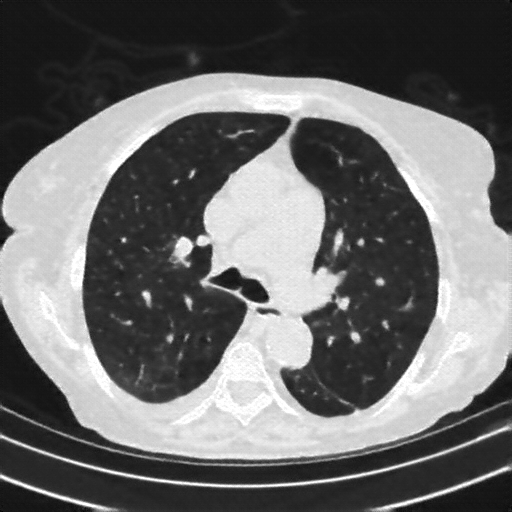

Targeted Slice 70 - Lung Window Analysis (Generated vs Real Venous)

0.583

Lung SSIM

161.5

Lung RMSE

72.4

Lung MAE

Average Lung Window Metrics Across All Slices (153 slices) - Generated vs Real Venous

0.553

Lung SSIM (Avg)

147.1

Lung RMSE (Avg)

69.0

Lung MAE (Avg)

Generated VENOUS CT scan (A→B translation)

Lung window (WL -600, WW 1500 β†’ Low βˆ’1350, High +150)

Mediastinum window (WL 40, WW 400 β†’ Low βˆ’160, High +240)